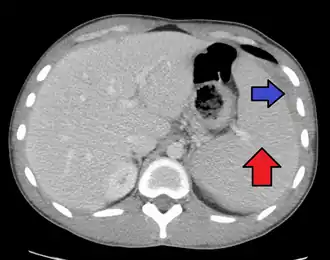

Spleen enlargement is common in the second and third weeks, although this may not be apparent on physical examination. Rarely, the spleen may rupture.[27] There may also be some enlargement of the liver.[25] Jaundice occurs only occasionally.[16][28]

Splenomegaly is a common symptom of infectious mononucleosis, and healthcare providers may consider using abdominal ultrasonography to get insight into the enlargement of a person's spleen.[61] However, because spleen size varies greatly, ultrasonography is not a valid technique for assessing spleen enlargement. It should not be used in typical circumstances or to make routine decisions about fitness for playing sports.[61]